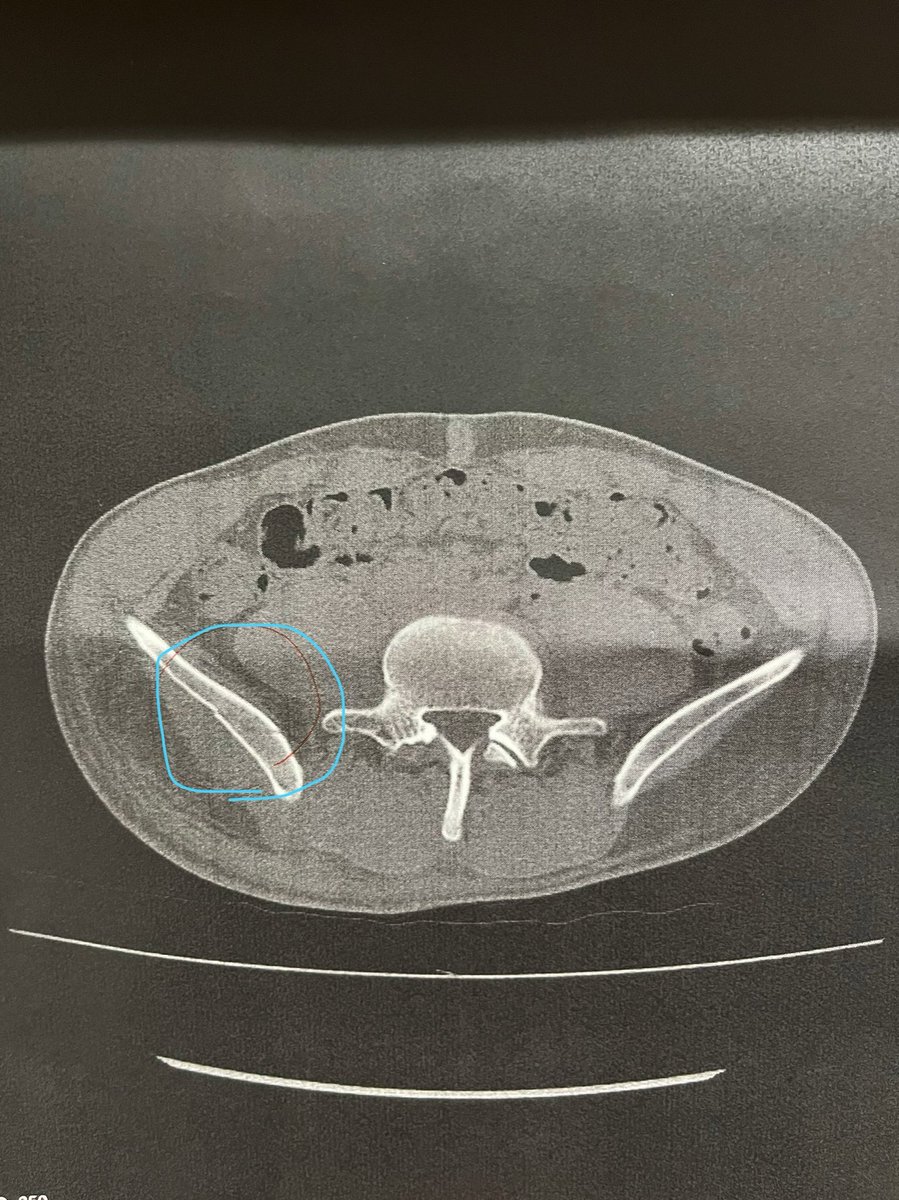

蹴られた場所が紫になり腫れてきました。 なぜか妻が落書きし、関係ない場所に息子が落書きしました。 上の方の縦線は胸椎骨折の手術後です。

今日の精密検査の結果。右腸骨翼骨折でした。 経験上骨折してないと思う言ってたのに、経験値が足りてませんでした😭 安静が必要という事で今日から入院となりました。

僕の腰は馬のキックに負けました。